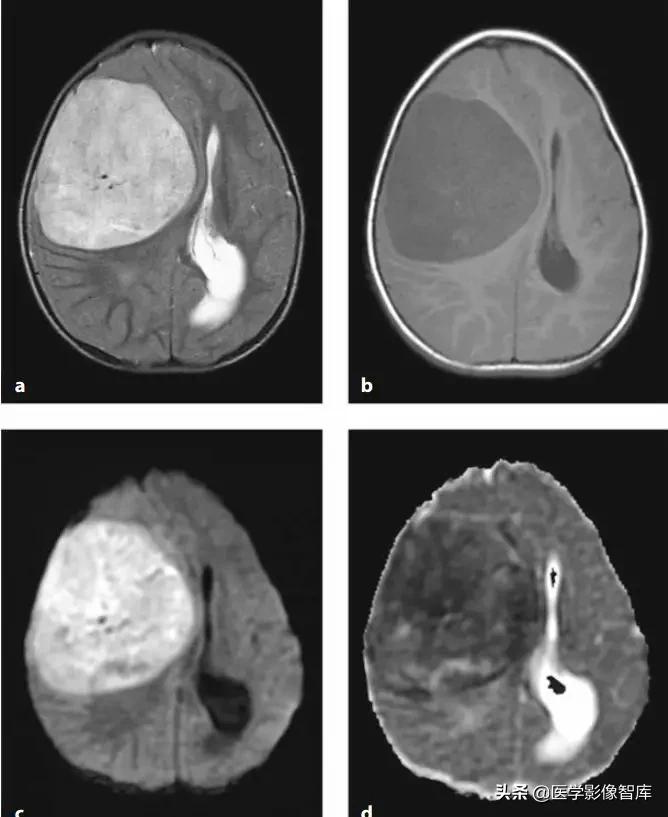

图13 中枢神经细胞瘤(肿瘤细胞密集,DWI高、ADC低)